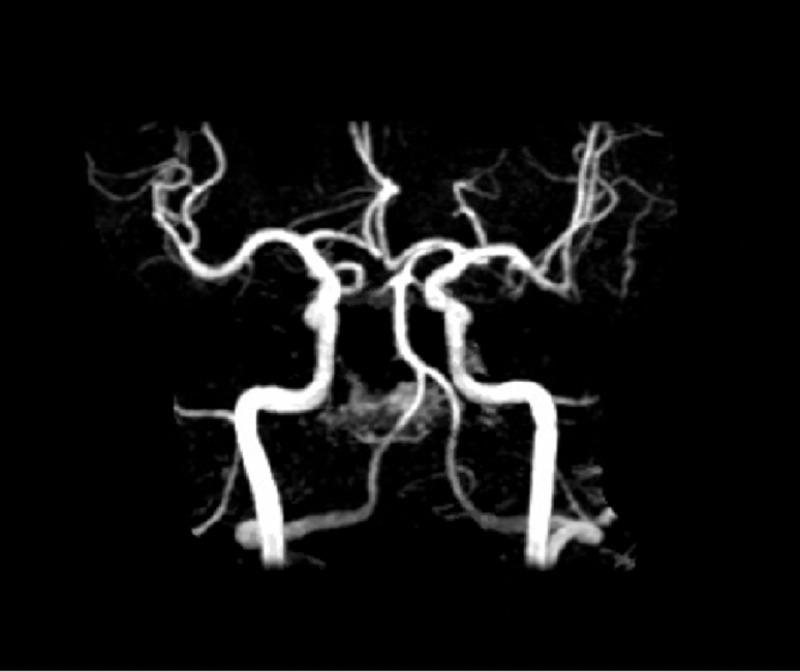

自发性冠状动脉夹层:年轻男性ST段抬高型心肌梗死的罕见病因。

Spontaneous Coronary Artery Dissection: An Unusual Cause of ST-Elevation Myocardial Infarction in Young Males.

Spontaneous coronary artery dissection (SCAD) is a non-traumatic, non-iatrogenic, and non-atherosclerotic coronary artery disorder that manifests clinically as an acute coronary syndrome (ACS), arrhythmia, or sudden cardiac death (SCD). It is a rare cause of ACS (1.7-4%) and SCD (0.5%), more commonly in women than men. It is rarely reported in males. We report a case of acute ST-elevation myocardial infarction (STEMI) due to SCAD in a 44-year-old healthy male.

摘要

自发性冠状动脉夹层(SCAD)是一种非创伤性、非医源性且非动脉粥样硬化性的冠状动脉疾病,临床上表现为急性冠状动脉综合征(ACS)、心律失常或心源性猝死(SCD)。它是ACS(1.7 - 4%)和SCD(0.5%)的罕见病因,女性比男性更常见。男性中鲜有报道。我们报告一例44岁健康男性因SCAD导致的急性ST段抬高型心肌梗死(STEMI)病例。